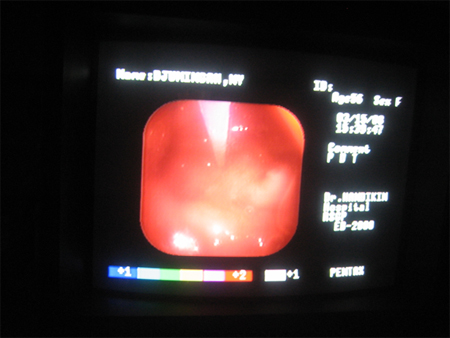

手術噹中的胃鏡截圖